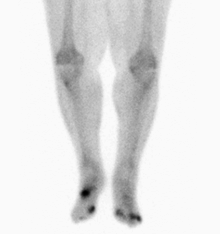

Nuclear medicine scans can be a helpful adjunct to MRI in patients who have metallic hardware that limits or prevents effective magnetic resonance. Generally a triple phase technetium 99 based scan will show increased uptake on all three phases. Gallium scans are 100% sensitive for osteomyelitis but not specific, and may be helpful in patients with metallic prostheses. Combined WBC imaging with marrow studies have 90% accuracy in diagnosing osteomyelitis.[14]